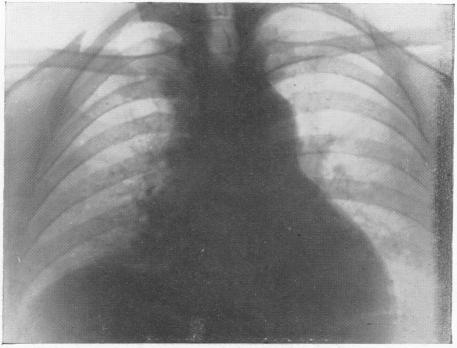

THE EFFECT OF OBSTRUCTED RESPIRATION ON HEART AND LUNGS: ITS CLINICAL IMPORTANCE IN RADIOGRAPHY.

Br Med J. 1929 Mar 9;1(3557):439-438.2. doi: 10.1136/bmj.1.3557.439.